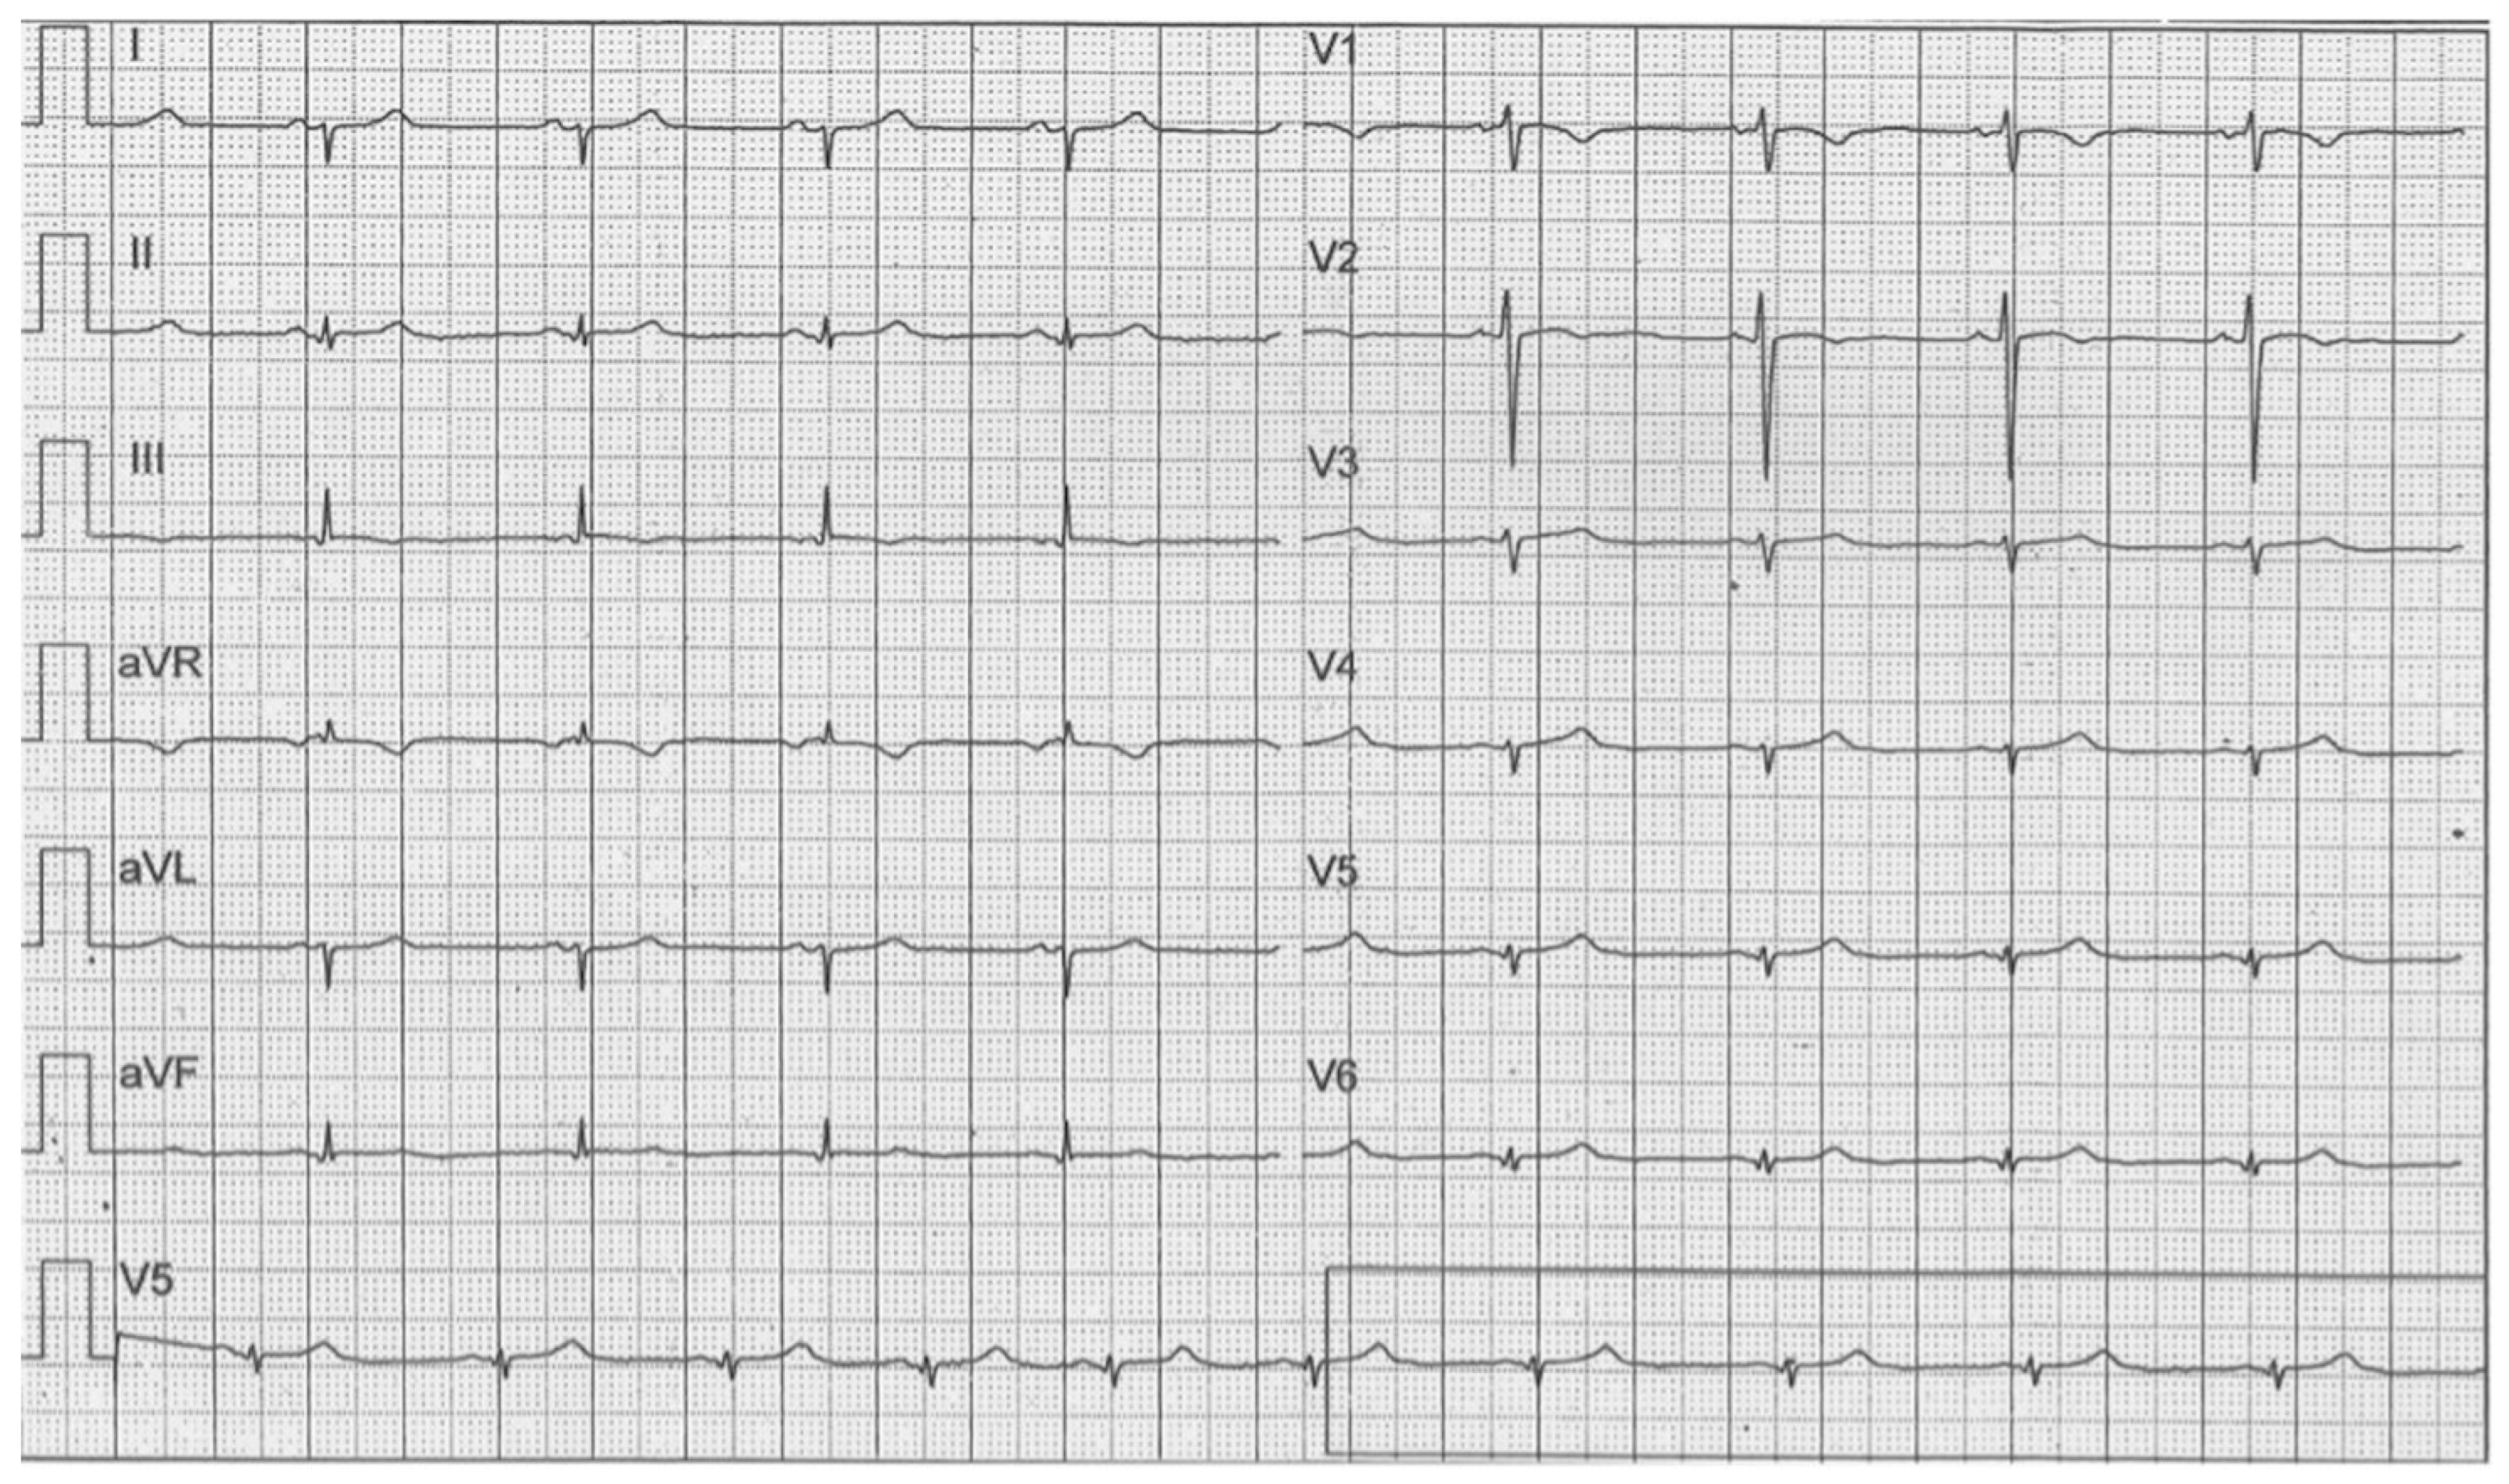

3. Case 2